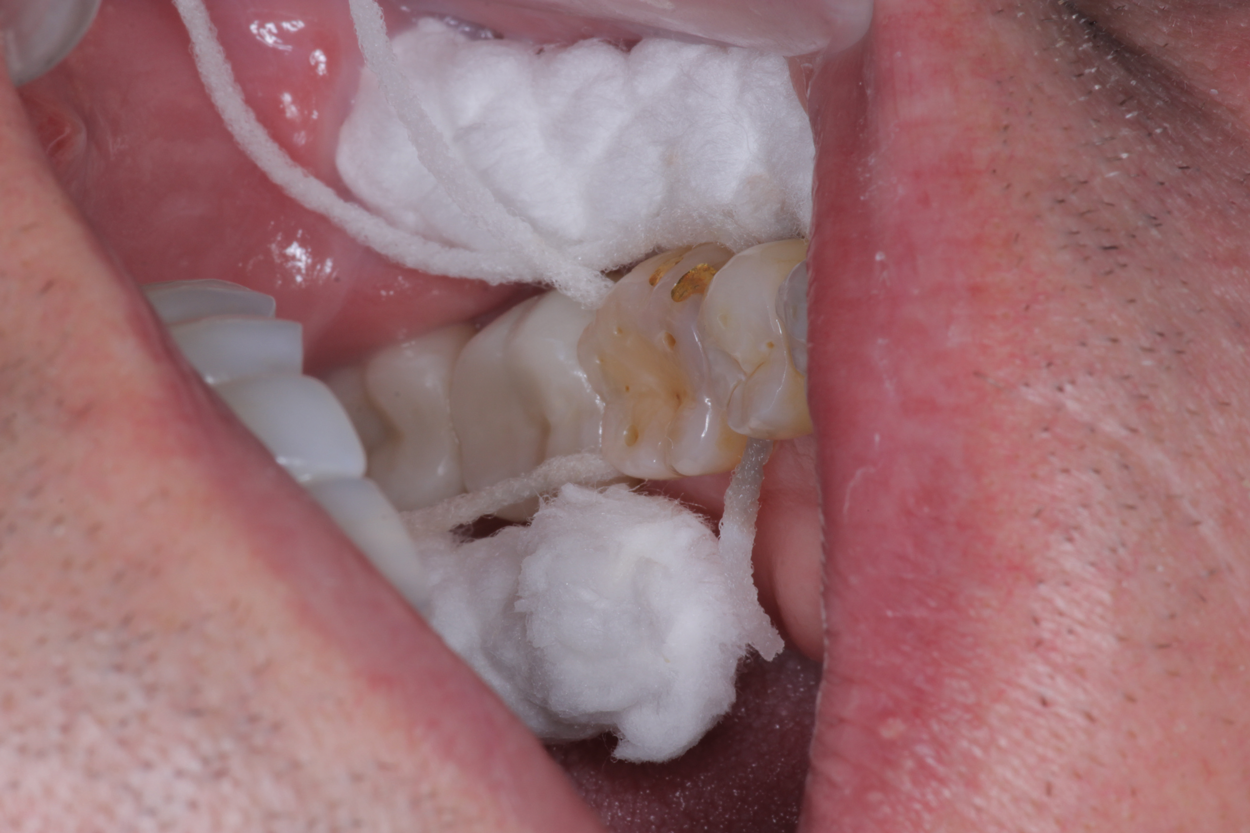

A 56-year-old female patient required an extensive treatment plan, including multiple crowns and fillings in each quadrant. She was able to complete treatment only in stages. By the time one quadrant was completed, she began to have pain on the mesial of tooth No. 20 (Figure 1 and Figure 2). Because the patient had no more dental benefits for the year, she needed to alleviate the sensitivity and prevent further problems between appointments. The doctor recommended SDF to stave off the sensitivity she was experiencing and to prevent growth of the lesion. Silver diamine fluoride was placed during a restorative appointment, and her sensitivity and pain subsided. When she returned a month later for her hygiene visit, she stated her pain had returned. A second SDF treatment was administered, which prevented the pain from returning a third time, until her restorative treatment could resume.

(1.) Patient exhbitied pain on the mesial of tooth No. 20.

Figure 1

(2.) Patient required an extensive treatment plan, including multiple crowns and fillings in each quadrant.

Figure 2